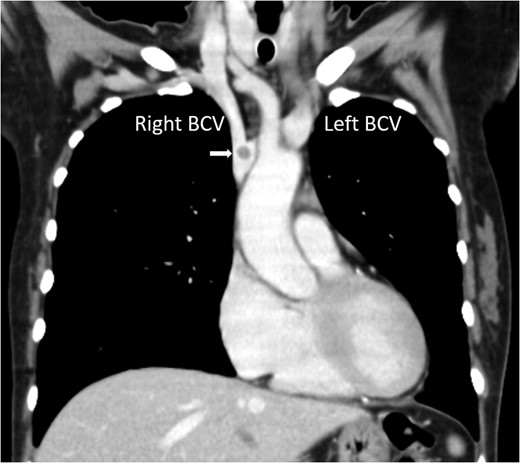

Chest computed tomography showing a nodule at the junction of the right and left BCV (arrow).